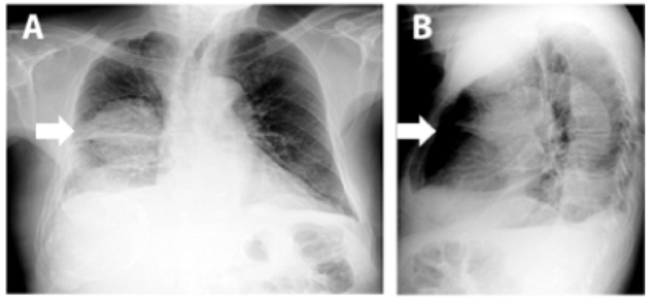

La radiografía de tórax mostró infiltrado intersticial difuso con tractos de fibrosis y engrosamiento pleural; a nivel apical derecho se evidenciaron varias imágenes radiolúcidas que podían estar en relación con bullas. A nivel parahiliar derecho se observa imagen radio-opaca bien definida con diámetro >5cm que pudiese estar en relación con masa pulmonar (Figura 2A). La imagen lateral mostró signos de atrapamiento aéreo, rectificación del arco medio, aorta elongada y ateromatosa y osteopenia generalizada (Figura 2B).